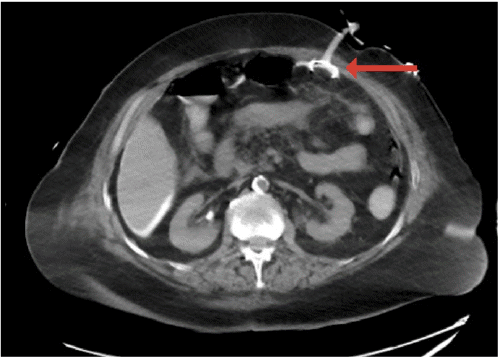

One hour after initiating PEG tube feeds, the patient developed pain, flushing, and emesis. Tube feeds were immediately discontinued due to clinical concerns for peritonitis. Initial X ray with contrast of the abdomen and pelvis visualized contrast outlining the stomach and duodenum; however, tube placement was indeterminant due to artifact. Subsequent CT scan with PEG tube contrast showed intraperitoneal free air, diffuse intraperitoneal contrast extravasation (Figure 1A), and the tube button lying outside of the gastric lumen adjacent to the inner surface of the abdominal wall (Figure 1B).

Figure 1. Abdominopelvic CT Scan with PEG Tube Contrast. Published with Permission

B.

B) Percutaneous endoscopic gastrostomy (PEG) tube button outside gastric lumen (red arrow)